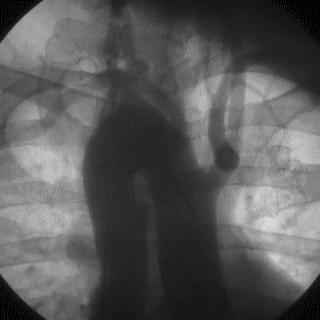

操作:升主动脉造影,寻找静脉桥血管

➢ CASE 3

AL1.0

➢ CASE 4

➢ CASE 5

升主动脉造影未见桥血管显影,原位血管造影也没发现竞争血流迹象,可以确定桥血管已闭塞,必要时可以借助冠脉CTA辅助诊断